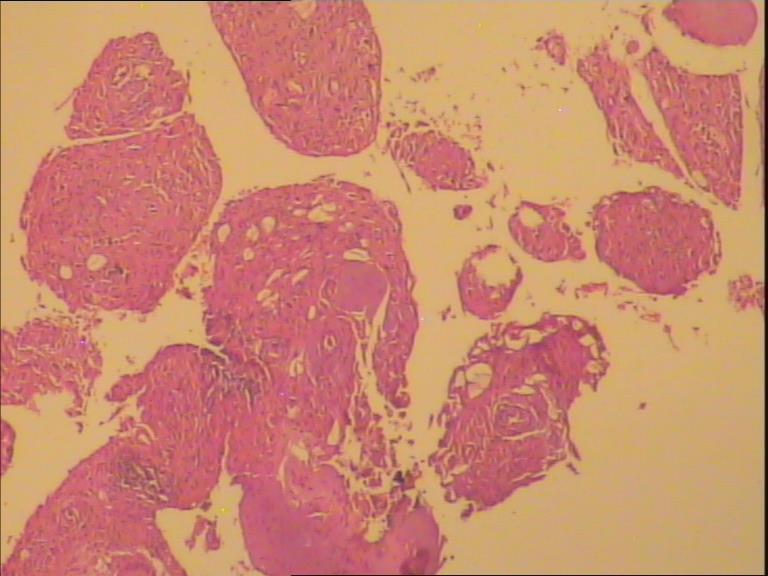

骨巨细胞瘤1级

膝关节置换术后7年,疼痛6月。 术中见关节假体周围大量增生肉样、葡萄状组织。是否有骨质浸润手术医生说不清楚,X片未见骨质浸润。

膝关节腔内肿物

灰白组织一堆直径7cm,部份组织呈葡萄样。

那些颗粒状物是假体脱下来的碎屑,巨细胞首先考虑是反应性的。

会诊意见:见大量组织细胞,多核j巨细胞反应,未见明确肿瘤性病变。